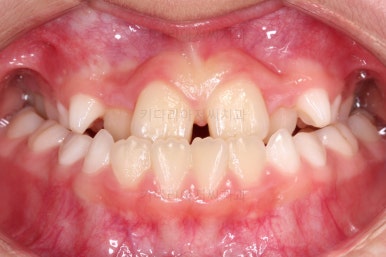

마찬가지로 초진 시 입안의 모습이에요.

아래 앞니가 윗니보다 앞에 있는 "반대교합" 즉, 거꾸로 물려있는 상황이었고요.

어금니 쪽을 보시면(왼쪽 위 사진) 윗니 어금니도 아래 어금니보다 안쪽으로 들어와 있는 "어금니 반대교합"도 있는 상황이었어요.

즉, 윗니가 있는 위턱뼈가 3차원적으로 작은 상황이었던거죠.

이렇게 아랫니들이 윗니보다 앞으로 나와있는 형태의 부정교합을 "앵글씨 3급" 부정교합이라고 합니다.